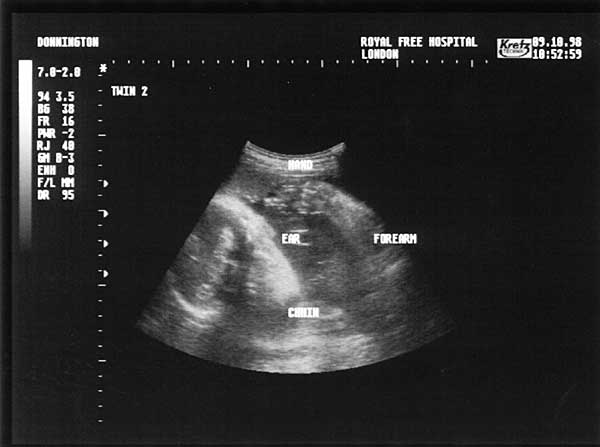

28 Weeks - Friday 9th October 1998.

Twenty Eight Week Scan 2